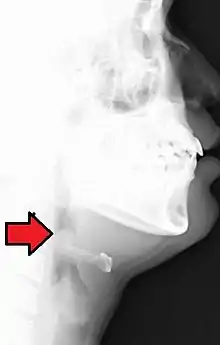

| Lateral radiograph showing the "thumb sign". The diagnosis of epiglottitis was confirmed on subsequent imaging and laryngoscopy. The patient recovered following treatment with prednisone and ceftriaxone | |

In radiology, the thumbprint sign, or thumbprinting, is a radiologic sign found on a radiograph that suggests the diagnosis of either epiglottitis or intestinal ischemia.

In a lateral C-spine radiograph, the sign is caused by a thickened free edge of the epiglottis, which causes it to appear more radiopaque than normal, resembling the distal thumb.